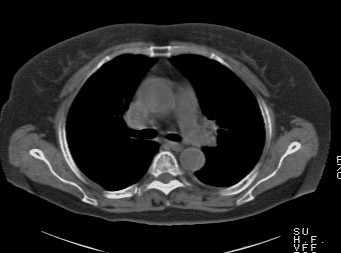

f,74发热咳嗽三天

考虑左肺上叶中央型肺癌并左肺上叶舌段肺不张。

考虑左肺上叶中央型肺癌并左肺上叶舌段肺不张.

左肺上叶舌段肺不张,建议作进一步检查除外中心型肺癌。

左肺上叶舌段肺不张,建议行纤支检查除外中心型肺癌。支持!